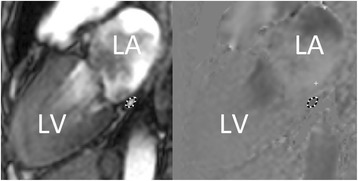

The coronary sinus flow (CSF) image plane was planned with guidance from a basal LV short-axis image as shown in Fig. 1. The image plane was defined to obtain a cross section of the coronary sinus as close as possible to the orifice in the right atrium to include as many LV cardiac veins as possible. The middle cardiac vein was included to measure the total flow of the whole LV. CSF was measured at rest and after 5 min of adenosine (Life Medical, Stockholm, Sweden) infusion (140 μg/kg/min) using phase-encoded breath-hold turbo field echo (TFE) velocity mapping sequence as previously described with a spatial resolution of (1.7–2.1) × (1.9–2.1) × (8-10 mm) and a VENC of 80 cm/s (rest) or 120–150 cm/s (stress) [14, 17, 18].

Fig. 1.

Typical example of coronary sinus delineation (dashed line) in a patient with systemic sclerosis (SSc). Left: Anatomical image; Right: Corresponding phase-contrast image. LA = Left atrium, LV = left ventricle

CMR image analysis

Images were analyzed using the image analysis software Segment version 2.0 R5014 [21, 22]. The coronary sinus was manually delineated in the phase images (Fig. 1, right panel) over the entire cardiac cycle to measure the total CSF (mL/min) of one cardiac cycle. The corresponding magnitude images were used for guidance to localize anatomical structures (Fig. 1, left panel). In four of the controls, the coronary sinus flow could not accurately be measured at rest due to a gracile coronary sinus. However, during adenosine hyperemia, the coronary sinus flow was successfully obtained in these controls.